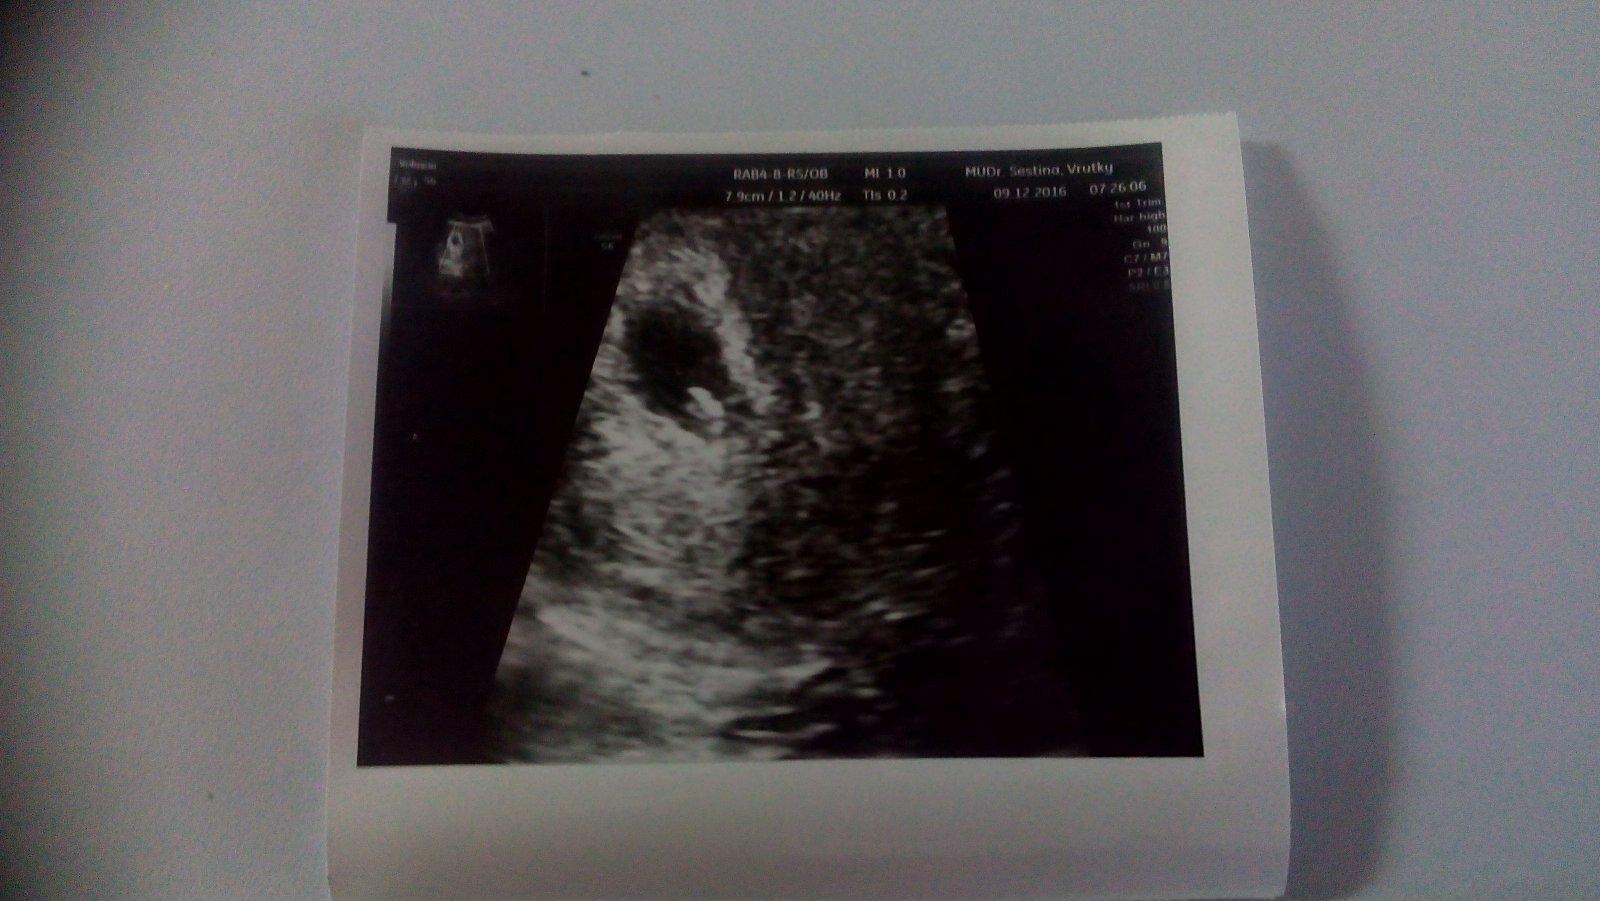

@luta13 ahoj tak mi už sme ráno boli na sone.posielam fotku drobčeka a videla som aj biť srdiečko niečo krásne to bolo 💜 podľa ms som 7+2 podla sona 6+2 a termín 26.7.2017 a 16.7 budeme mať s manželom 1.vyrocie a ntrapia má žiadne nevoľnosti okrem bolesti prsníkov tie bolia hrozne